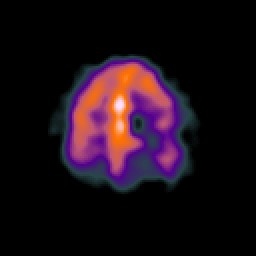

SPECT TC Study #1 -- Slice #40

[Home][Help][Clinical][Tour 1][Tour 2][Tour 3] Slice 40